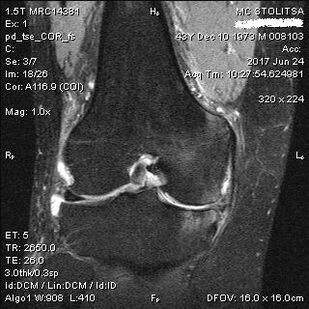

Die Diagnose einer Arthrose des Kniegelenks erfolgt in der Praxis eines Rheumatologen oder Orthopäden. Der Arzt untersucht das betroffene Gelenk, tastet es ab, hört sich Beschwerden an und stellt ergänzende Fragen. Führt mehrere Tests durch – fordert den Patienten beispielsweise auf, sein Bein zu beugen oder ein paar Schritte zu gehen. Wenn es dann notwendig ist, das Krankheitsstadium oder die Art der pathologischen Veränderungen zu klären, wird er Sie zu weiteren Untersuchungen überweisen. Zum Beispiel für die Computertomographie oder Radiographie.